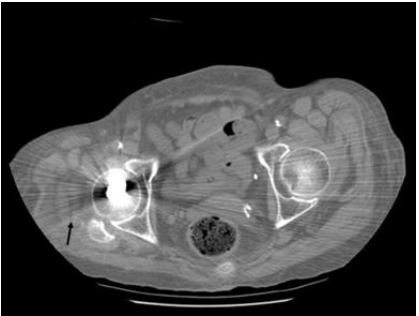

35.電腦斷層影像中,箭號所指屬於下列何種假影?

(A)motion artifacts (B)metal artifacts (C)truncation artifacts (D)partial-volume artifacts